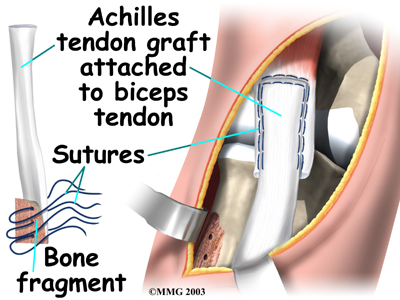

The surgeon then prepares a graft of tissue to lengthen the retracted biceps tendon. Some surgeons use a piece of hamstring tendon for the graft. Others use a section of the Achilles tendon where it attaches to the heel. This type of graft is usually an allograft, meaning that the tissue is taken from a cadaver (human tissue preserved for medical purposes).

When the is used, the surgeon leaves a small piece of the heel bone attached to the piece of tendon. Small holes are drilled into the piece of bone. Sutures are woven through these holes and will later be used to secure the end of the graft to the radial tuberosity. In this way, the graft will have a bone-to-bone connection that heals together. The healed bone solidly fixes the the graft to the radial tuberosity. After the graft is in place, its top end is then stitched over the front of the biceps muscle.

Next, the lower end of the graft is passed between the radius and ulna, exiting through the second incision that was made on the back of the forearm. The sutures from the bony end of the graft are threaded into holes that were drilled into the rim of the radial tuberosity earlier. The surgeon ties the sutures, to the radius.

When the surgeon is satisfied with the repair, the skin incisions are closed, and the elbow is placed in a protective brace.